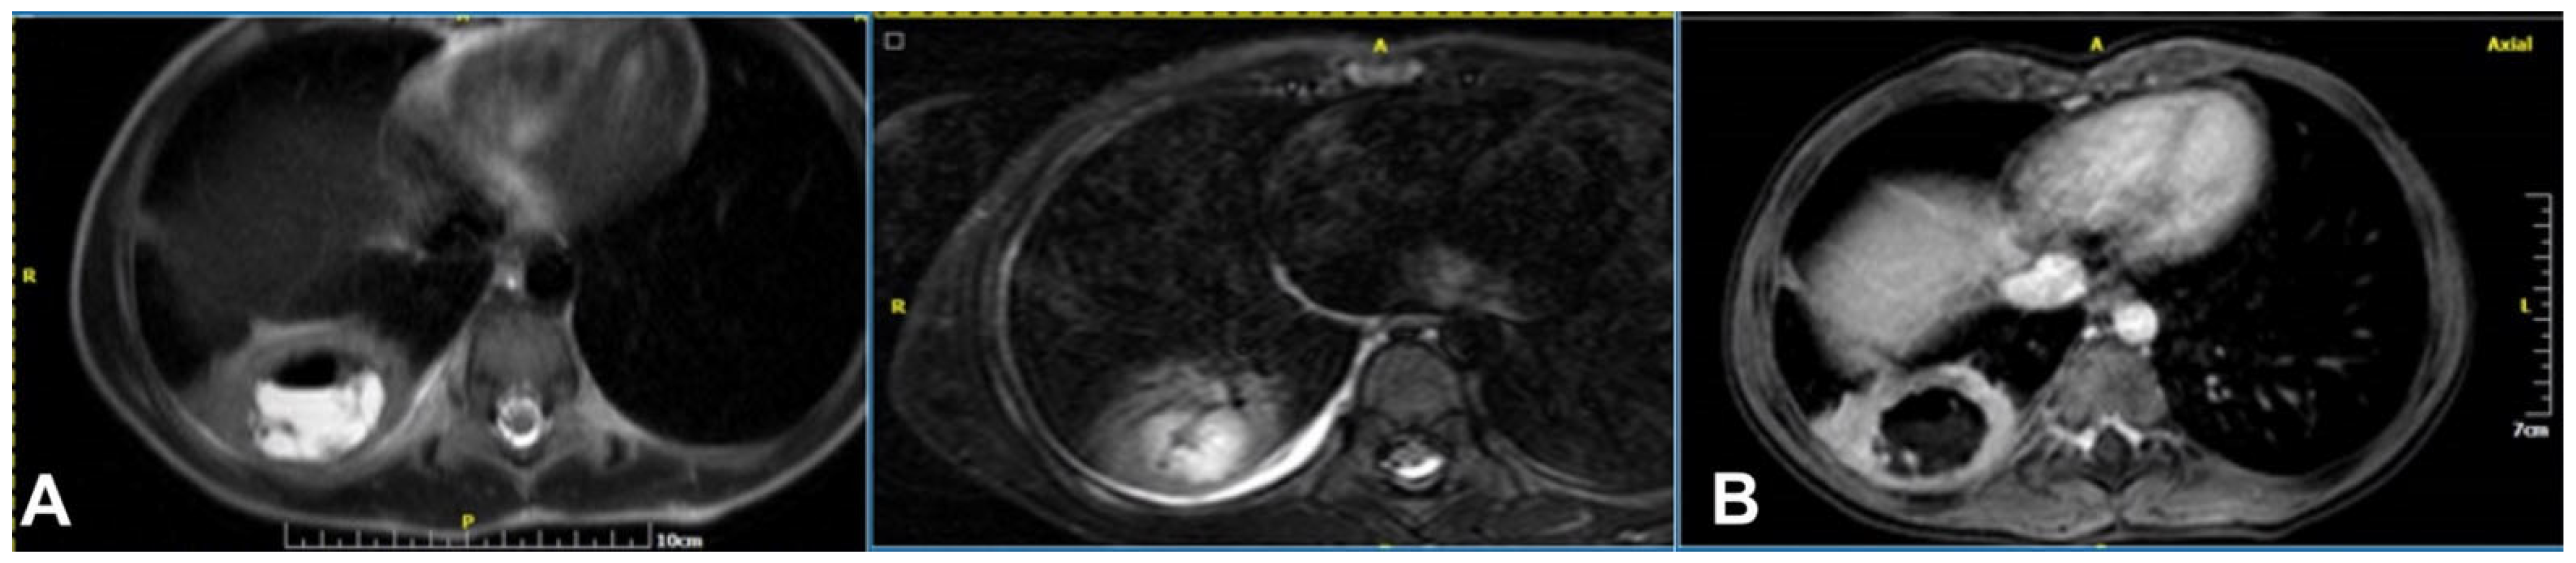

2.4.3. Necrotizing Pneumonia

2.4. Magnetic Resonance Imaging